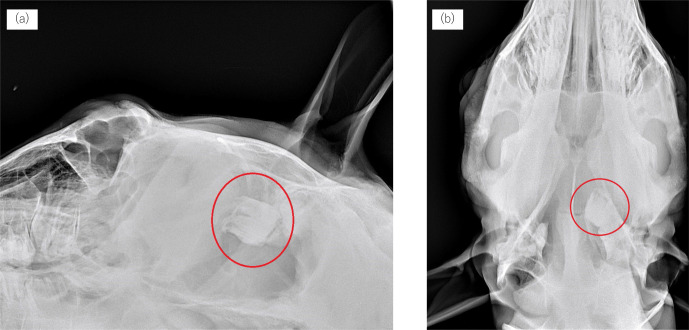

Computed tomography (CT) offers high-resolution, three-dimensional imaging, making it particularly valuable for assessing complex structures, such as the head, especially when conventional radiography and endoscopy are insufficient for a definitive diagnosis. Herein, we present two cases of equine cranial disorders resulting from congenital malformations. In case 1, which had a dentigerous cyst, CT images confirmed the location of the ectopic tooth within the skull and a detailed fistula tube. In case 2, which had temporohyoid osteoarthropathy, CT examination revealed that the stylohyoid bone was malformed, and the inner ear was presumed to be filled with soft tissue with calcification. The information obtained by CT was invaluable, as it allowed for accurate diagnosis and precise surgical planning.

计算机断层扫描(CT)提供高分辨率的三维成像,使其在评估复杂结构(如头部)时特别有价值,特别是当传统的x线摄影和内窥镜检查不足以进行明确诊断时。在此,我们提出了两个病例马颅疾病导致先天性畸形。病例1为含牙囊肿,CT图像确认了异位牙在颅骨内的位置和详细的瘘管。病例2为颞舌骨骨关节病,CT检查提示茎突舌骨畸形,推测内耳充盈有钙化软组织。CT所获得的信息是非常宝贵的,因为它允许准确的诊断和精确的手术计划。